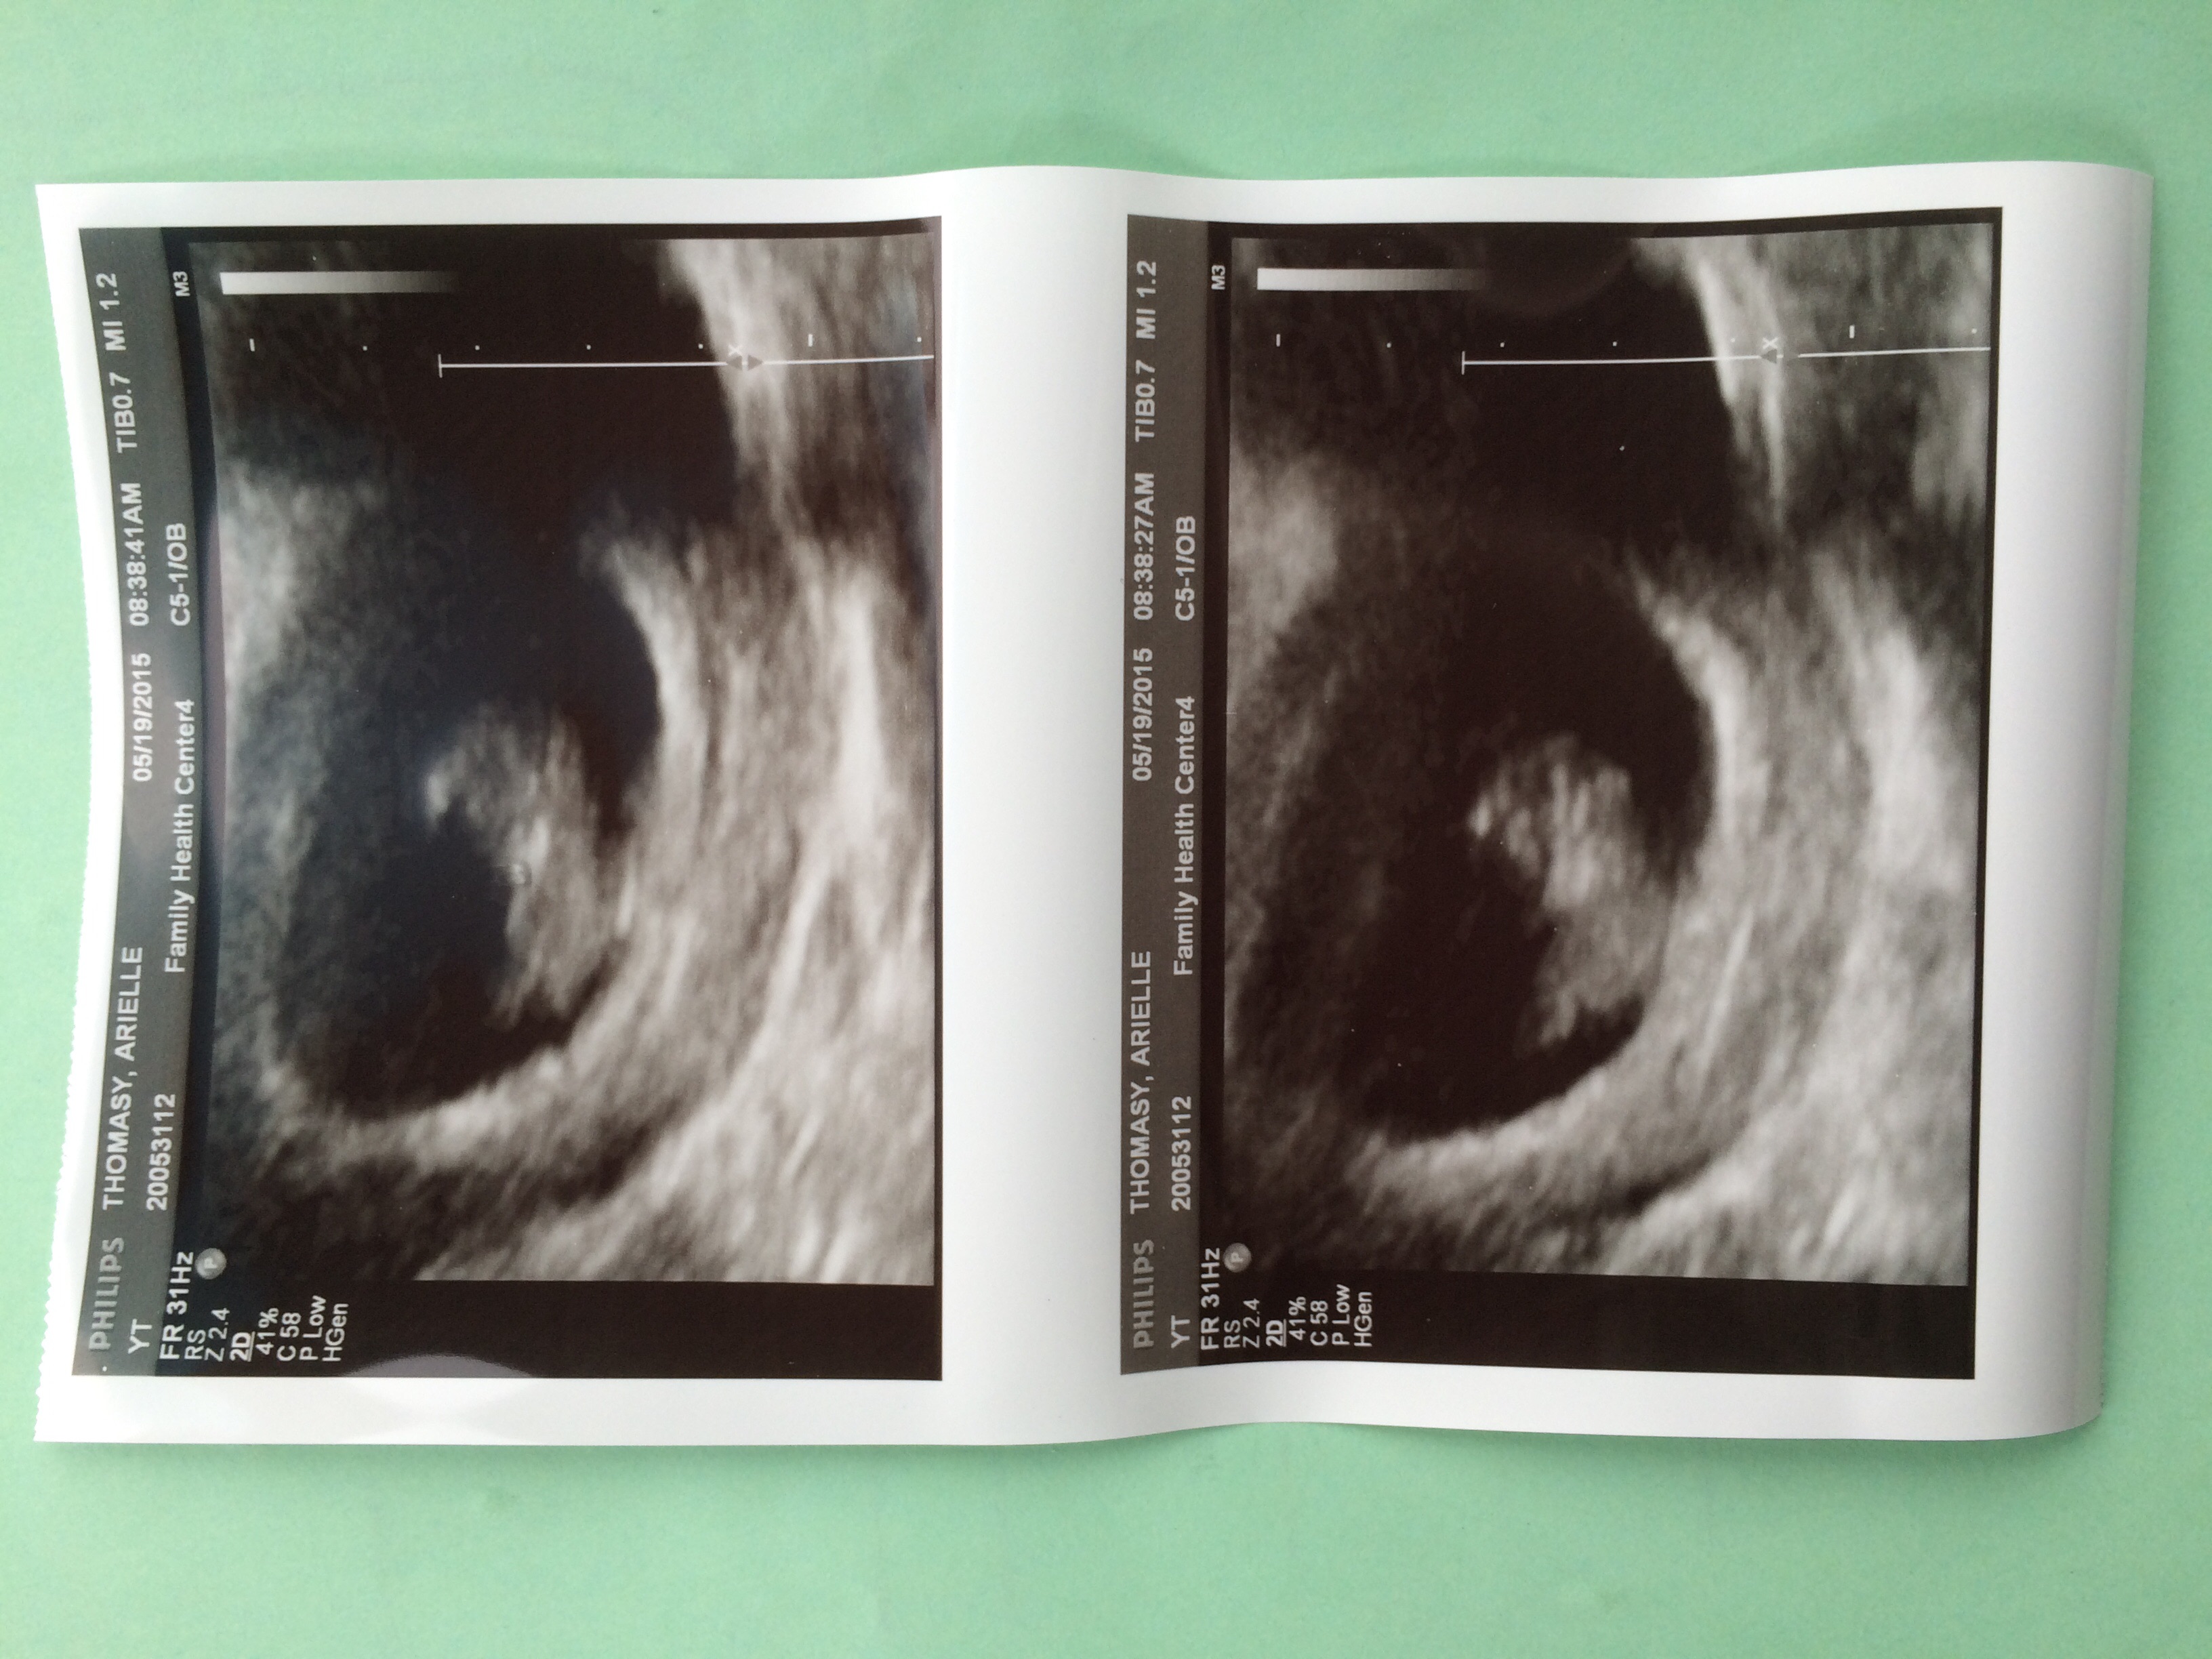

I thought I was 9 weeks today but am actually measuring at 8 weeks 3 days. My OB decided to keep the original due date since it's less than a week difference. Christmas Eve baby!